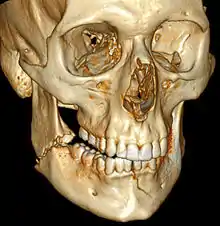

| 3D computed tomographic image of a mandible fracture in two places. One is a displaced right angle fracture and the other is a left parasymphyseal fracture. | |